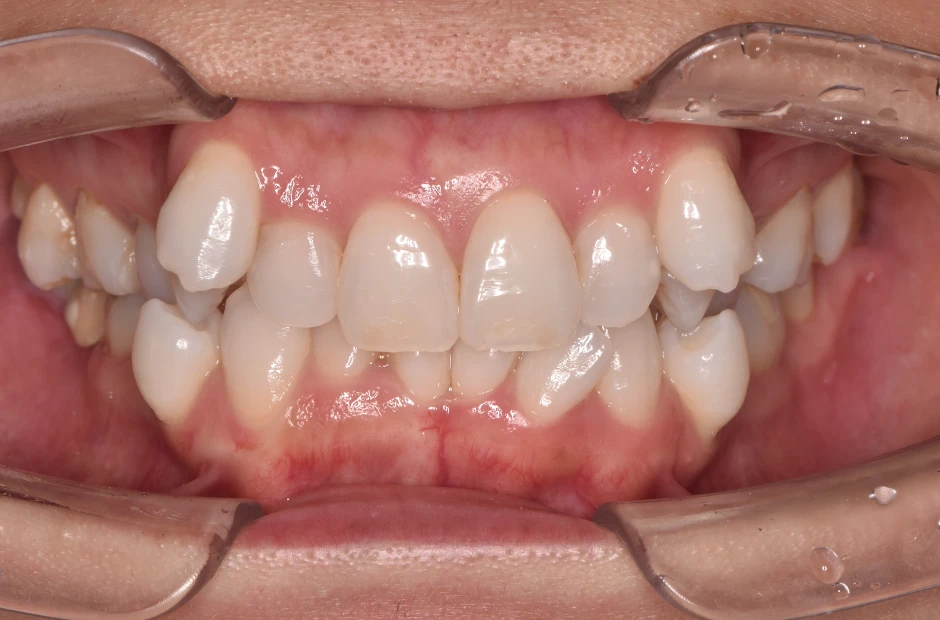

過剰歯

| 診断名・主訴 | でこぼこ |

|---|---|

| 年齢・性別 | 22歳・女性 |

| 治療期間・回数 | 1年6か月 |

| 治療に用いた主な装置 | リンガルブラケット |

| 抜歯部位 | 過剰歯 |

| 治療費 | 100万円(税抜) |

| リスク・副作用 | 装置による違和感・疼痛・歯肉退縮・歯根吸収・虫歯のリスクなど |

治療前

治療中

治療後